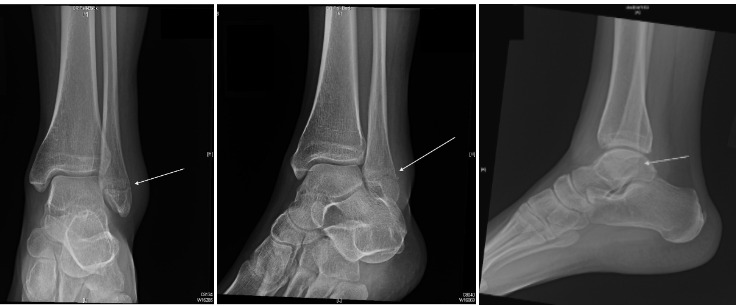

X-rays of the patient’s left ankle revealed a transverse fracture of the lateral malleolus (Figure 1).

On the Danis-Weber scale, this fracture would be classified as Type A, as it is inferior to the syndesmosis. These fractures are stable and typically do not require surgery.